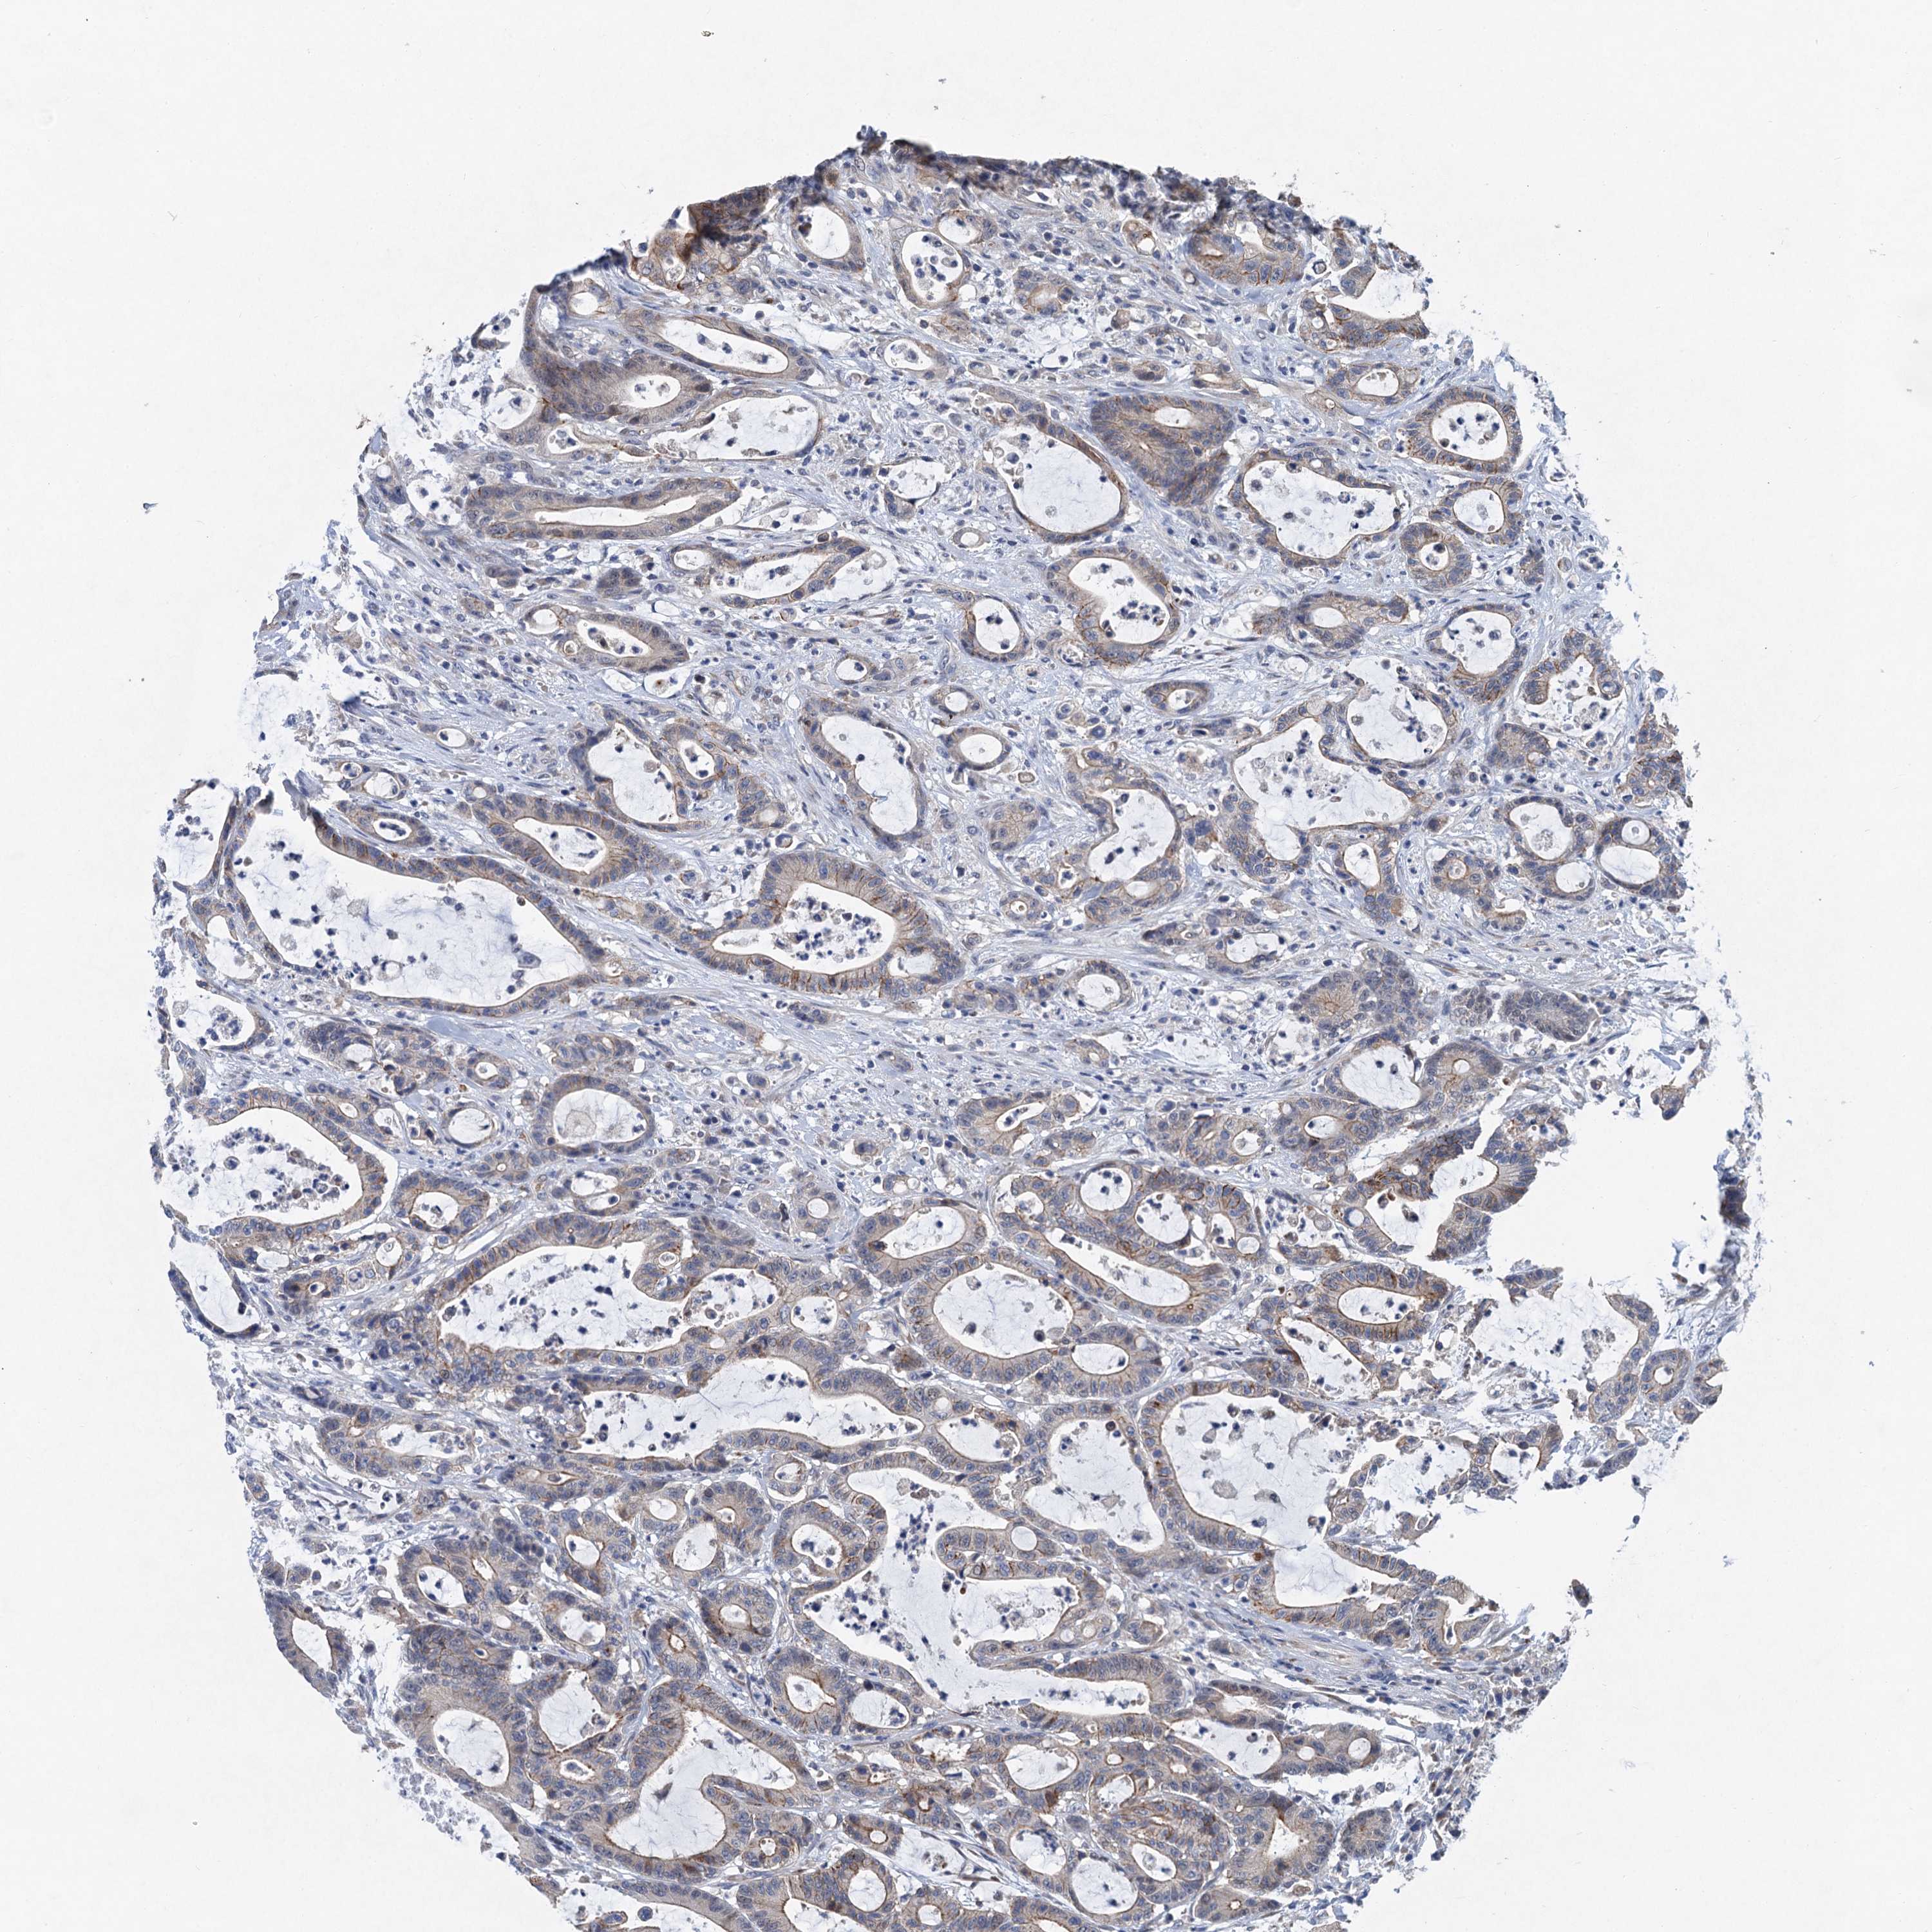

CANCER COLORECTAL CANCER Show tissue menu

Colorectal cancer

Human cancer

Colon adenocarcinoma